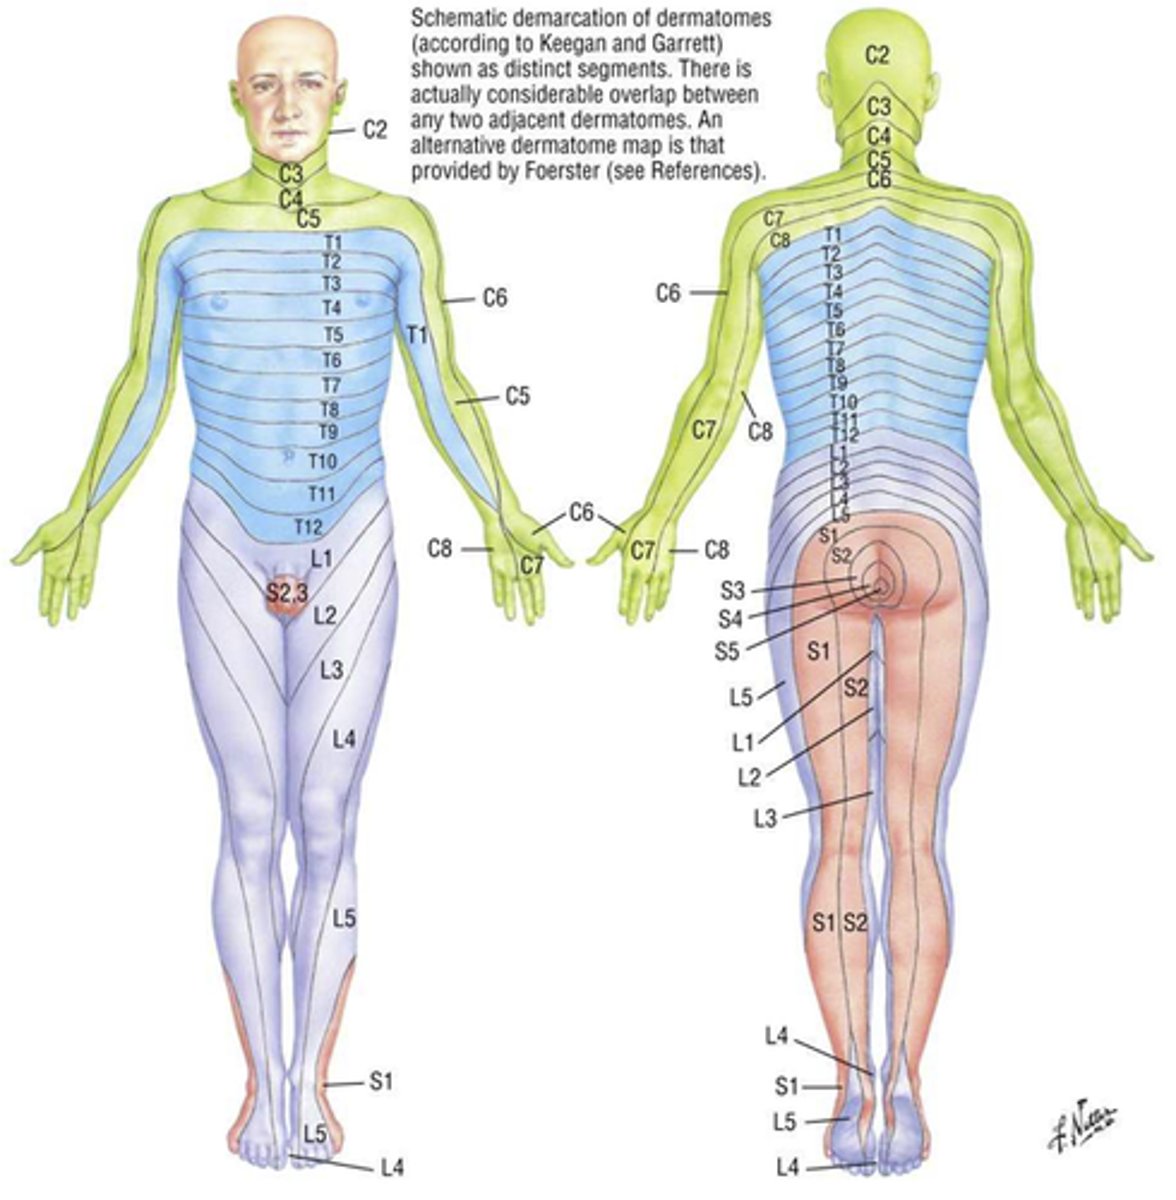

dermatome

Area of skin innervated by spinal nerves

sensory

Not face (CN V) or scalp

Some boundaries overlap

Shingles

varicella zoster virus

Causes chicken pox

Can later attack neurons in posterior roots and sensory ganglia